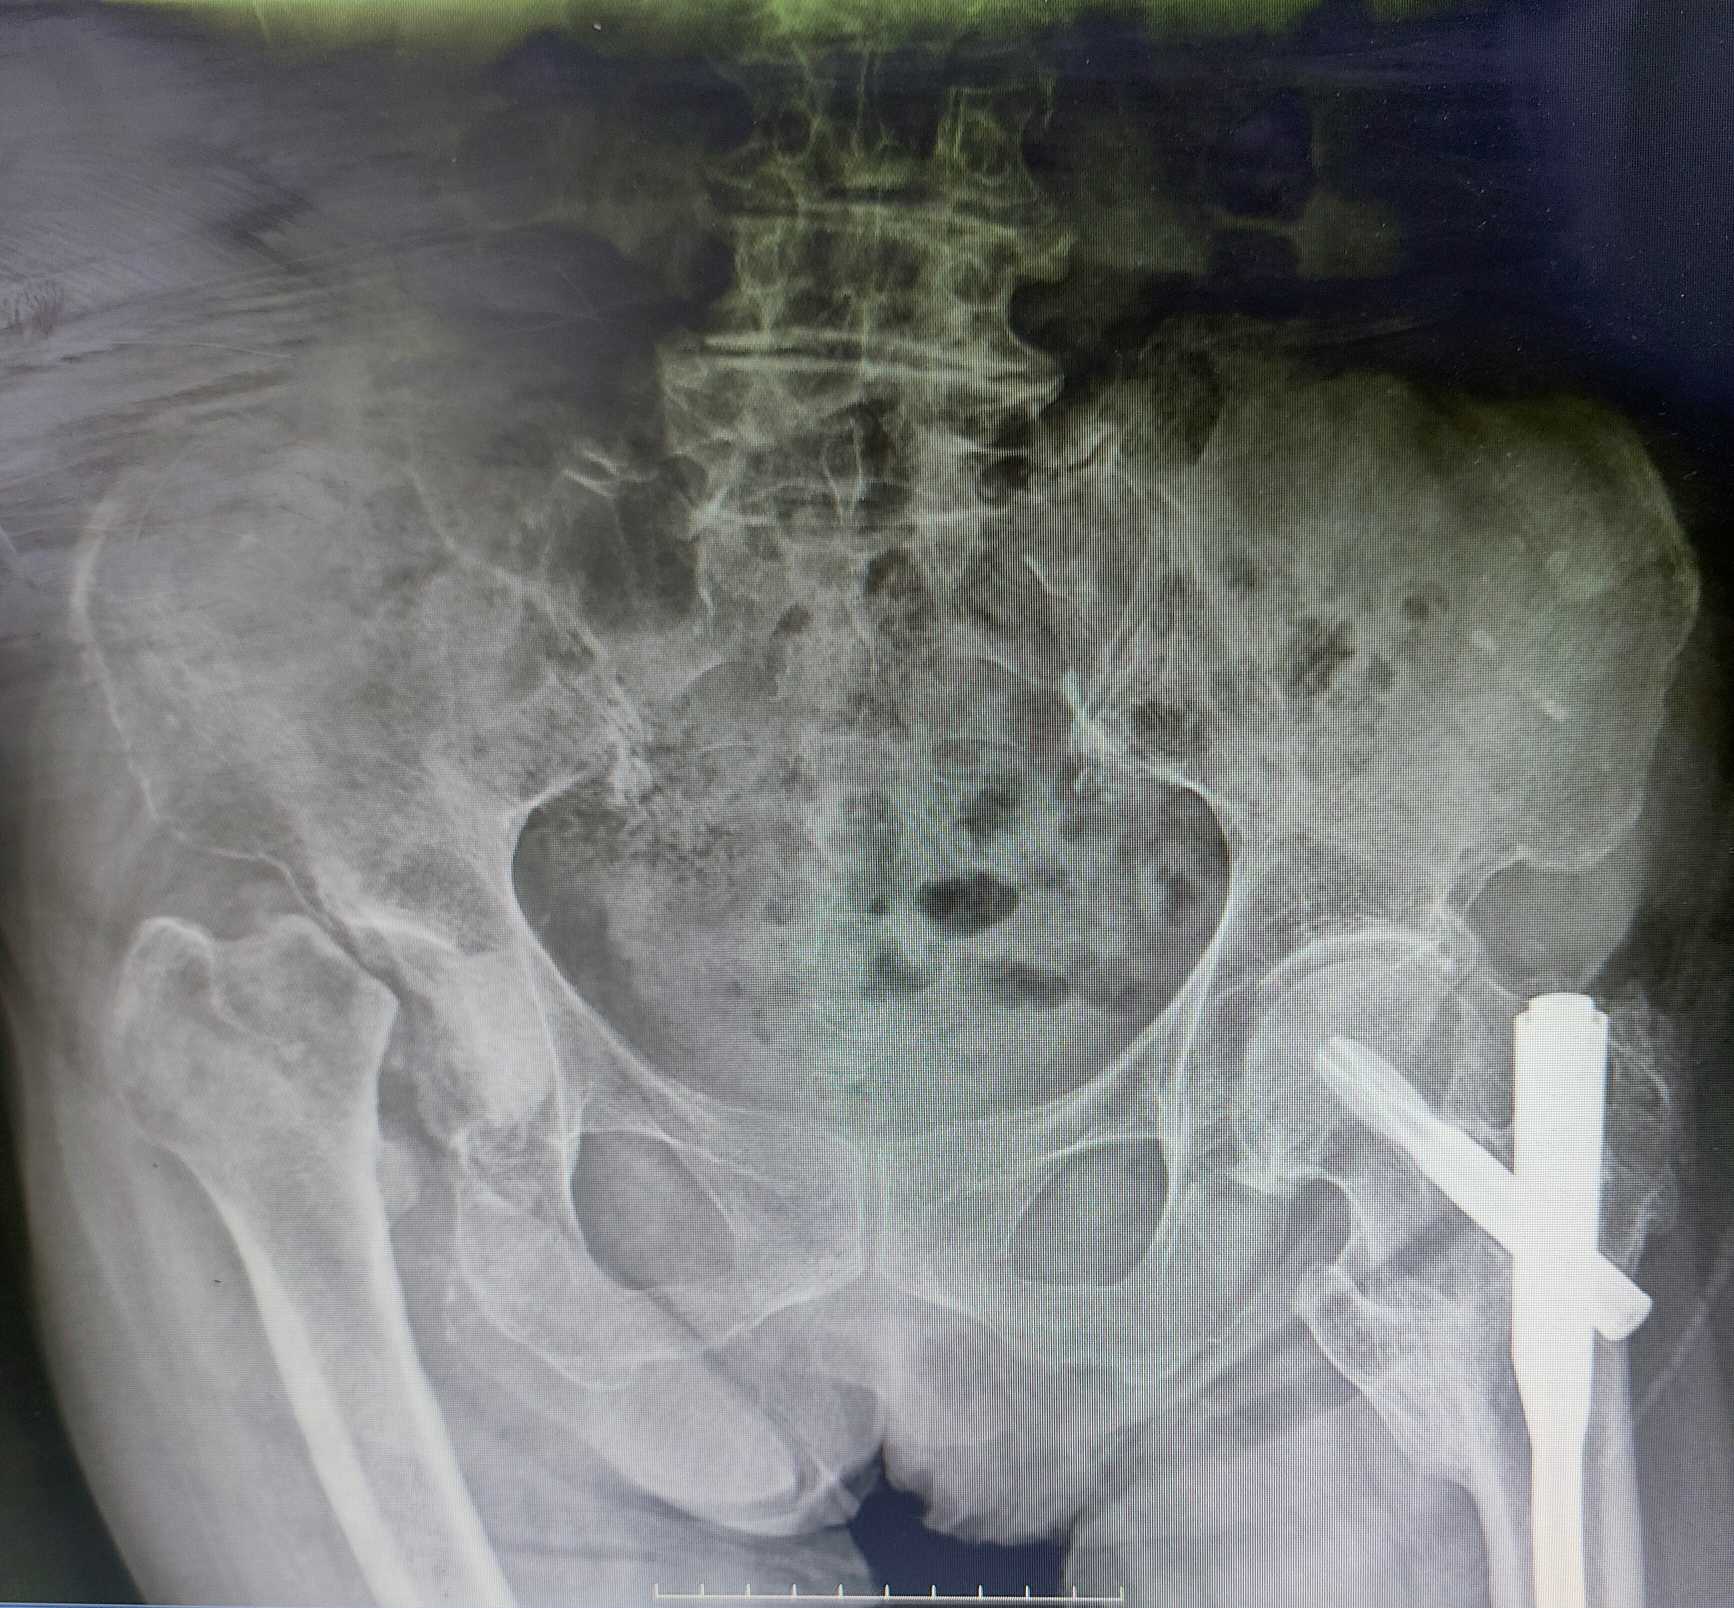

四个月后,患者在家属陪同下来到哈密市维吾尔医医院就诊。我院援疆专家马文龙接诊并确诊为右侧陈旧性股骨颈骨折、髋关节脱位、股骨头坏死及肢体屈曲内收挛缩短缩畸形。与患者及家属沟通后,决定进行手术治疗。

术前